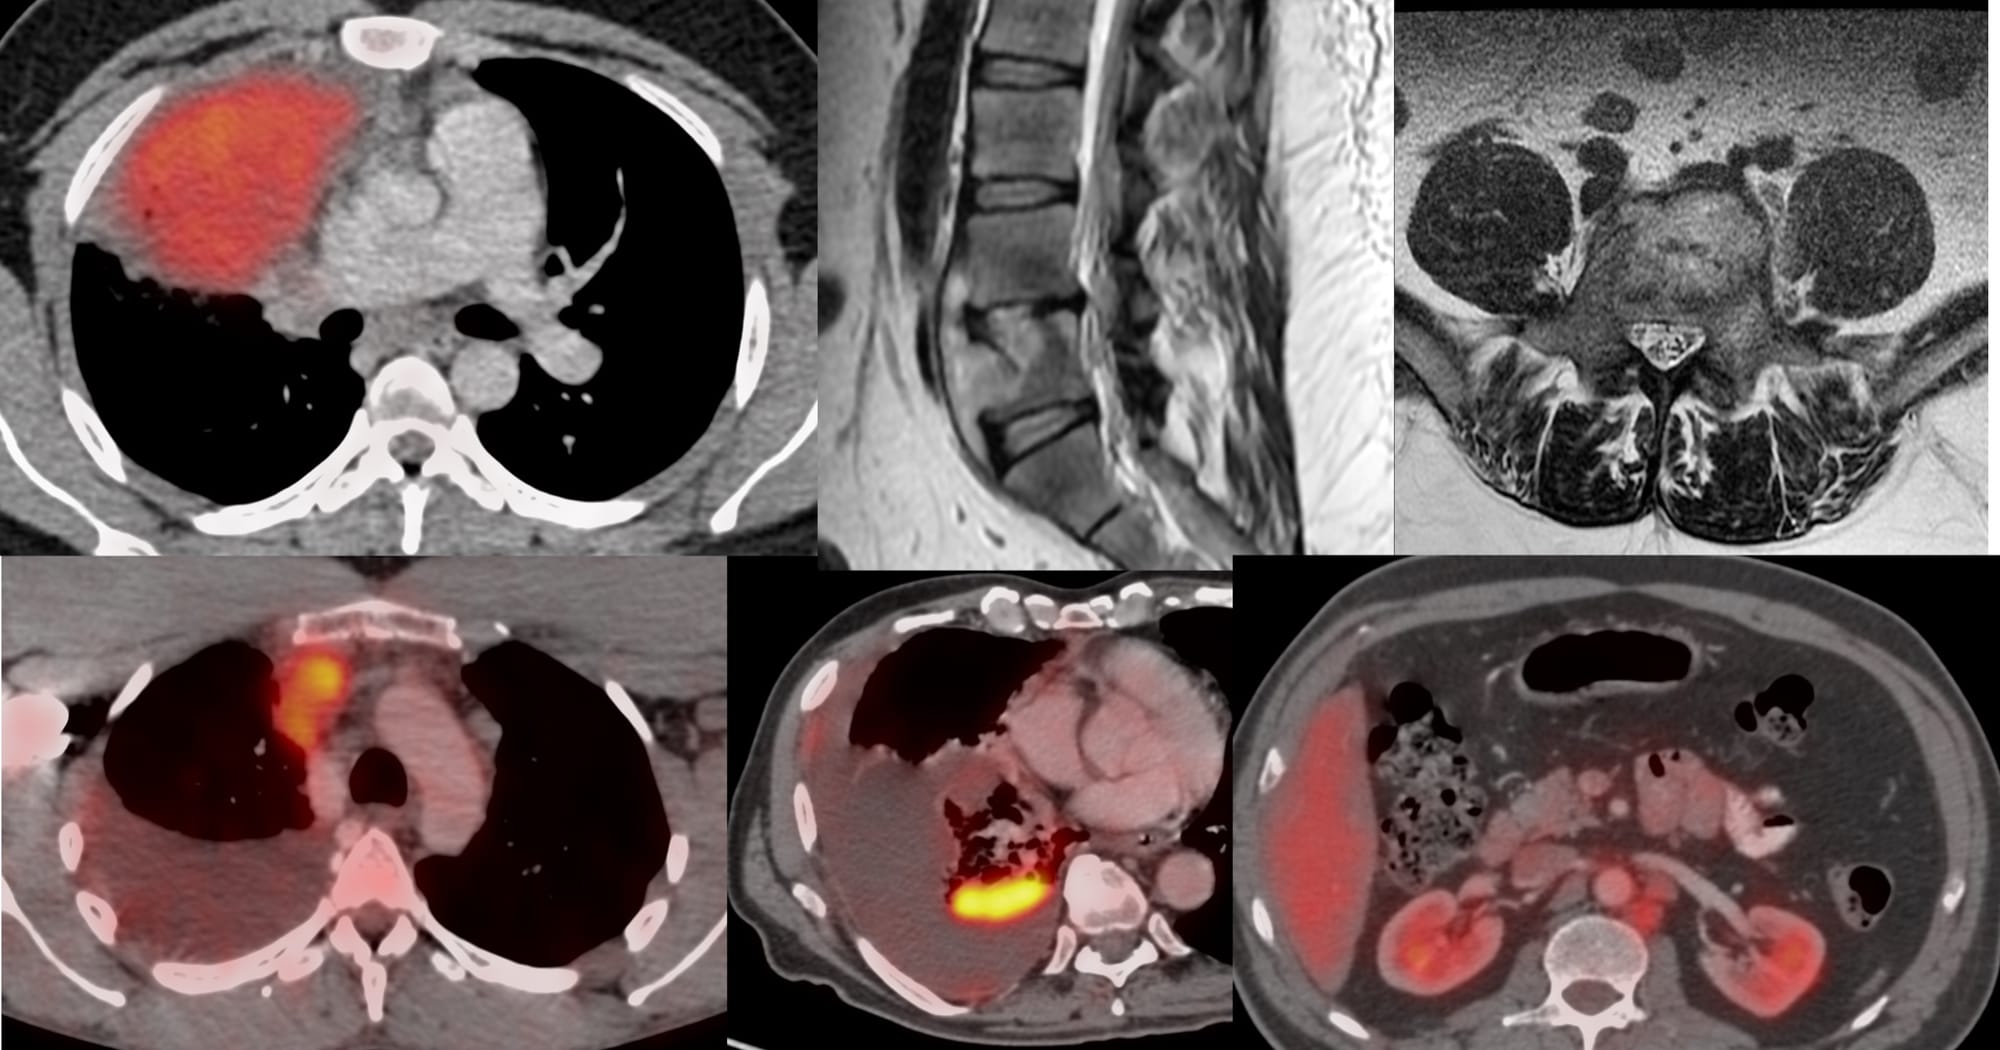

The 6 Cases for YouTube Live on 26 Feb at 7 PM Indian Standard Time